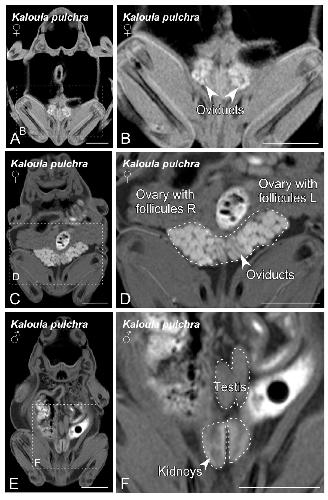

Sex Determination in Two Species of Anuran Amphibians by Magnetic Resonance Imaging and Ultrasound Techniques., Ruiz-Fernández MJ, Jiménez S, Fernández-Valle E, García-Real MI, Castejón D, Moreno N, Ardiaca M, Montesinos A, Ariza S, González-Soriano J., Animals (Basel). November 18, 2020; 10 (11):